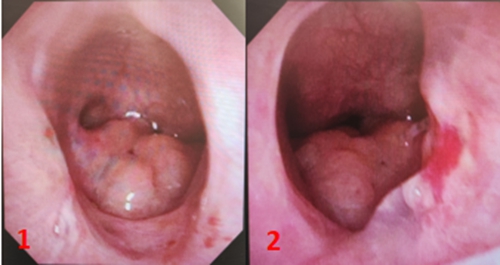

圖1、圖2:術(shù)后6周復(fù)查電子鼻咽鏡,鼻腔內(nèi)支架已完全降解,后鼻孔處結(jié)構(gòu)良好,黏膜光滑。